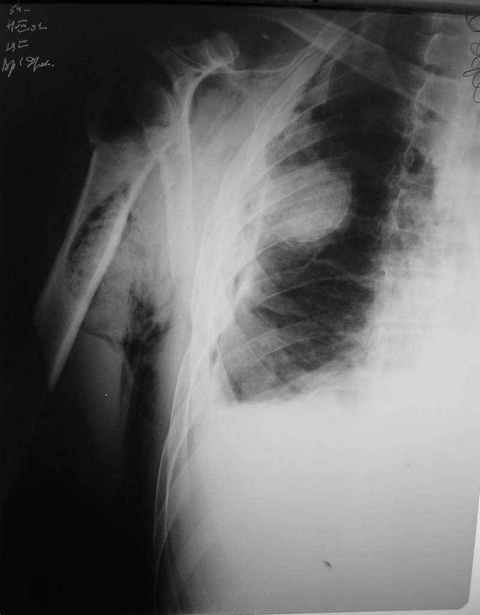

Правый плечевой сустав умеренно деформирован. По внутренней поверхности  плеча имеется кровоподтек. При пальпации плечевого сустава имеется умеренная болезненность. Активные и пассивные движения болезненные. Снижена чувствительность по тыльной поверхности пальцев кисти и отсутствует активное разгибание кисти и пальцев. Имеется подкожная эмфизема шеи, верхней половины грудной клетки (рис 1, 2). На рентгенограмме: оскольчатый перелом головки плечевой кости со значительным смещением, перелом 2-3 ребер справа, тканевая эмфизема (рис 3). КТ при поступлении: перелом головки плечевой кости в области анатомической шейки со смещением отломка головки в грудную полость, правосторонний гидроторакс, перелом 2-3-4 ребер справа. (рис 4). Через двое суток после поступления выполнена операция: атипичная торакотомия, эвакуация свернувшегося гемоторакса, удаление инородного тела (головки плечевой кости) из плевральной полости (при этом выявлено имеющееся повреждение париетального и висцерального листков плевры) (рис. 5), дренирование плевральной полости, замещение проксимального конца плечевой кости спейсером из костного цемента с антибиотиком (рис. 6). Послеоперационный период протекал гладко. При контрольной рентгенографии положение спейсера удовлетворительное (рис. 7, 8). Дренаж из плевральной полости удален через 3 суток после вмешательства. Послеоперационная рана зажила первичным натяжением. Через 12 дней после операции больной выписан на амбулаторное лечение.